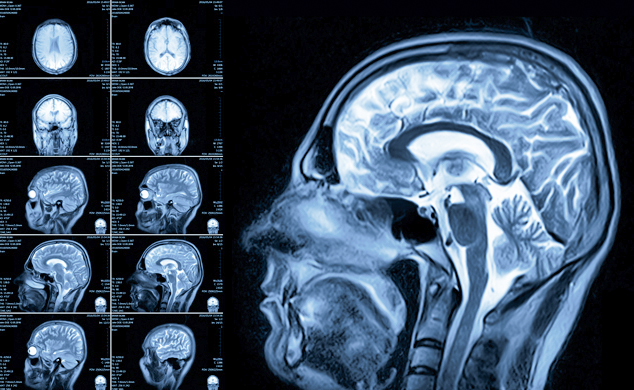

A través de la Resonancia Magnética se logra observar los órganos y la estructura de tejidos internos evitando el uso de Rayos X.

Se utilizan estas imágenes para diagnosticar una variedad de afecciones, desde rupturas de ligamentos hasta tumores.